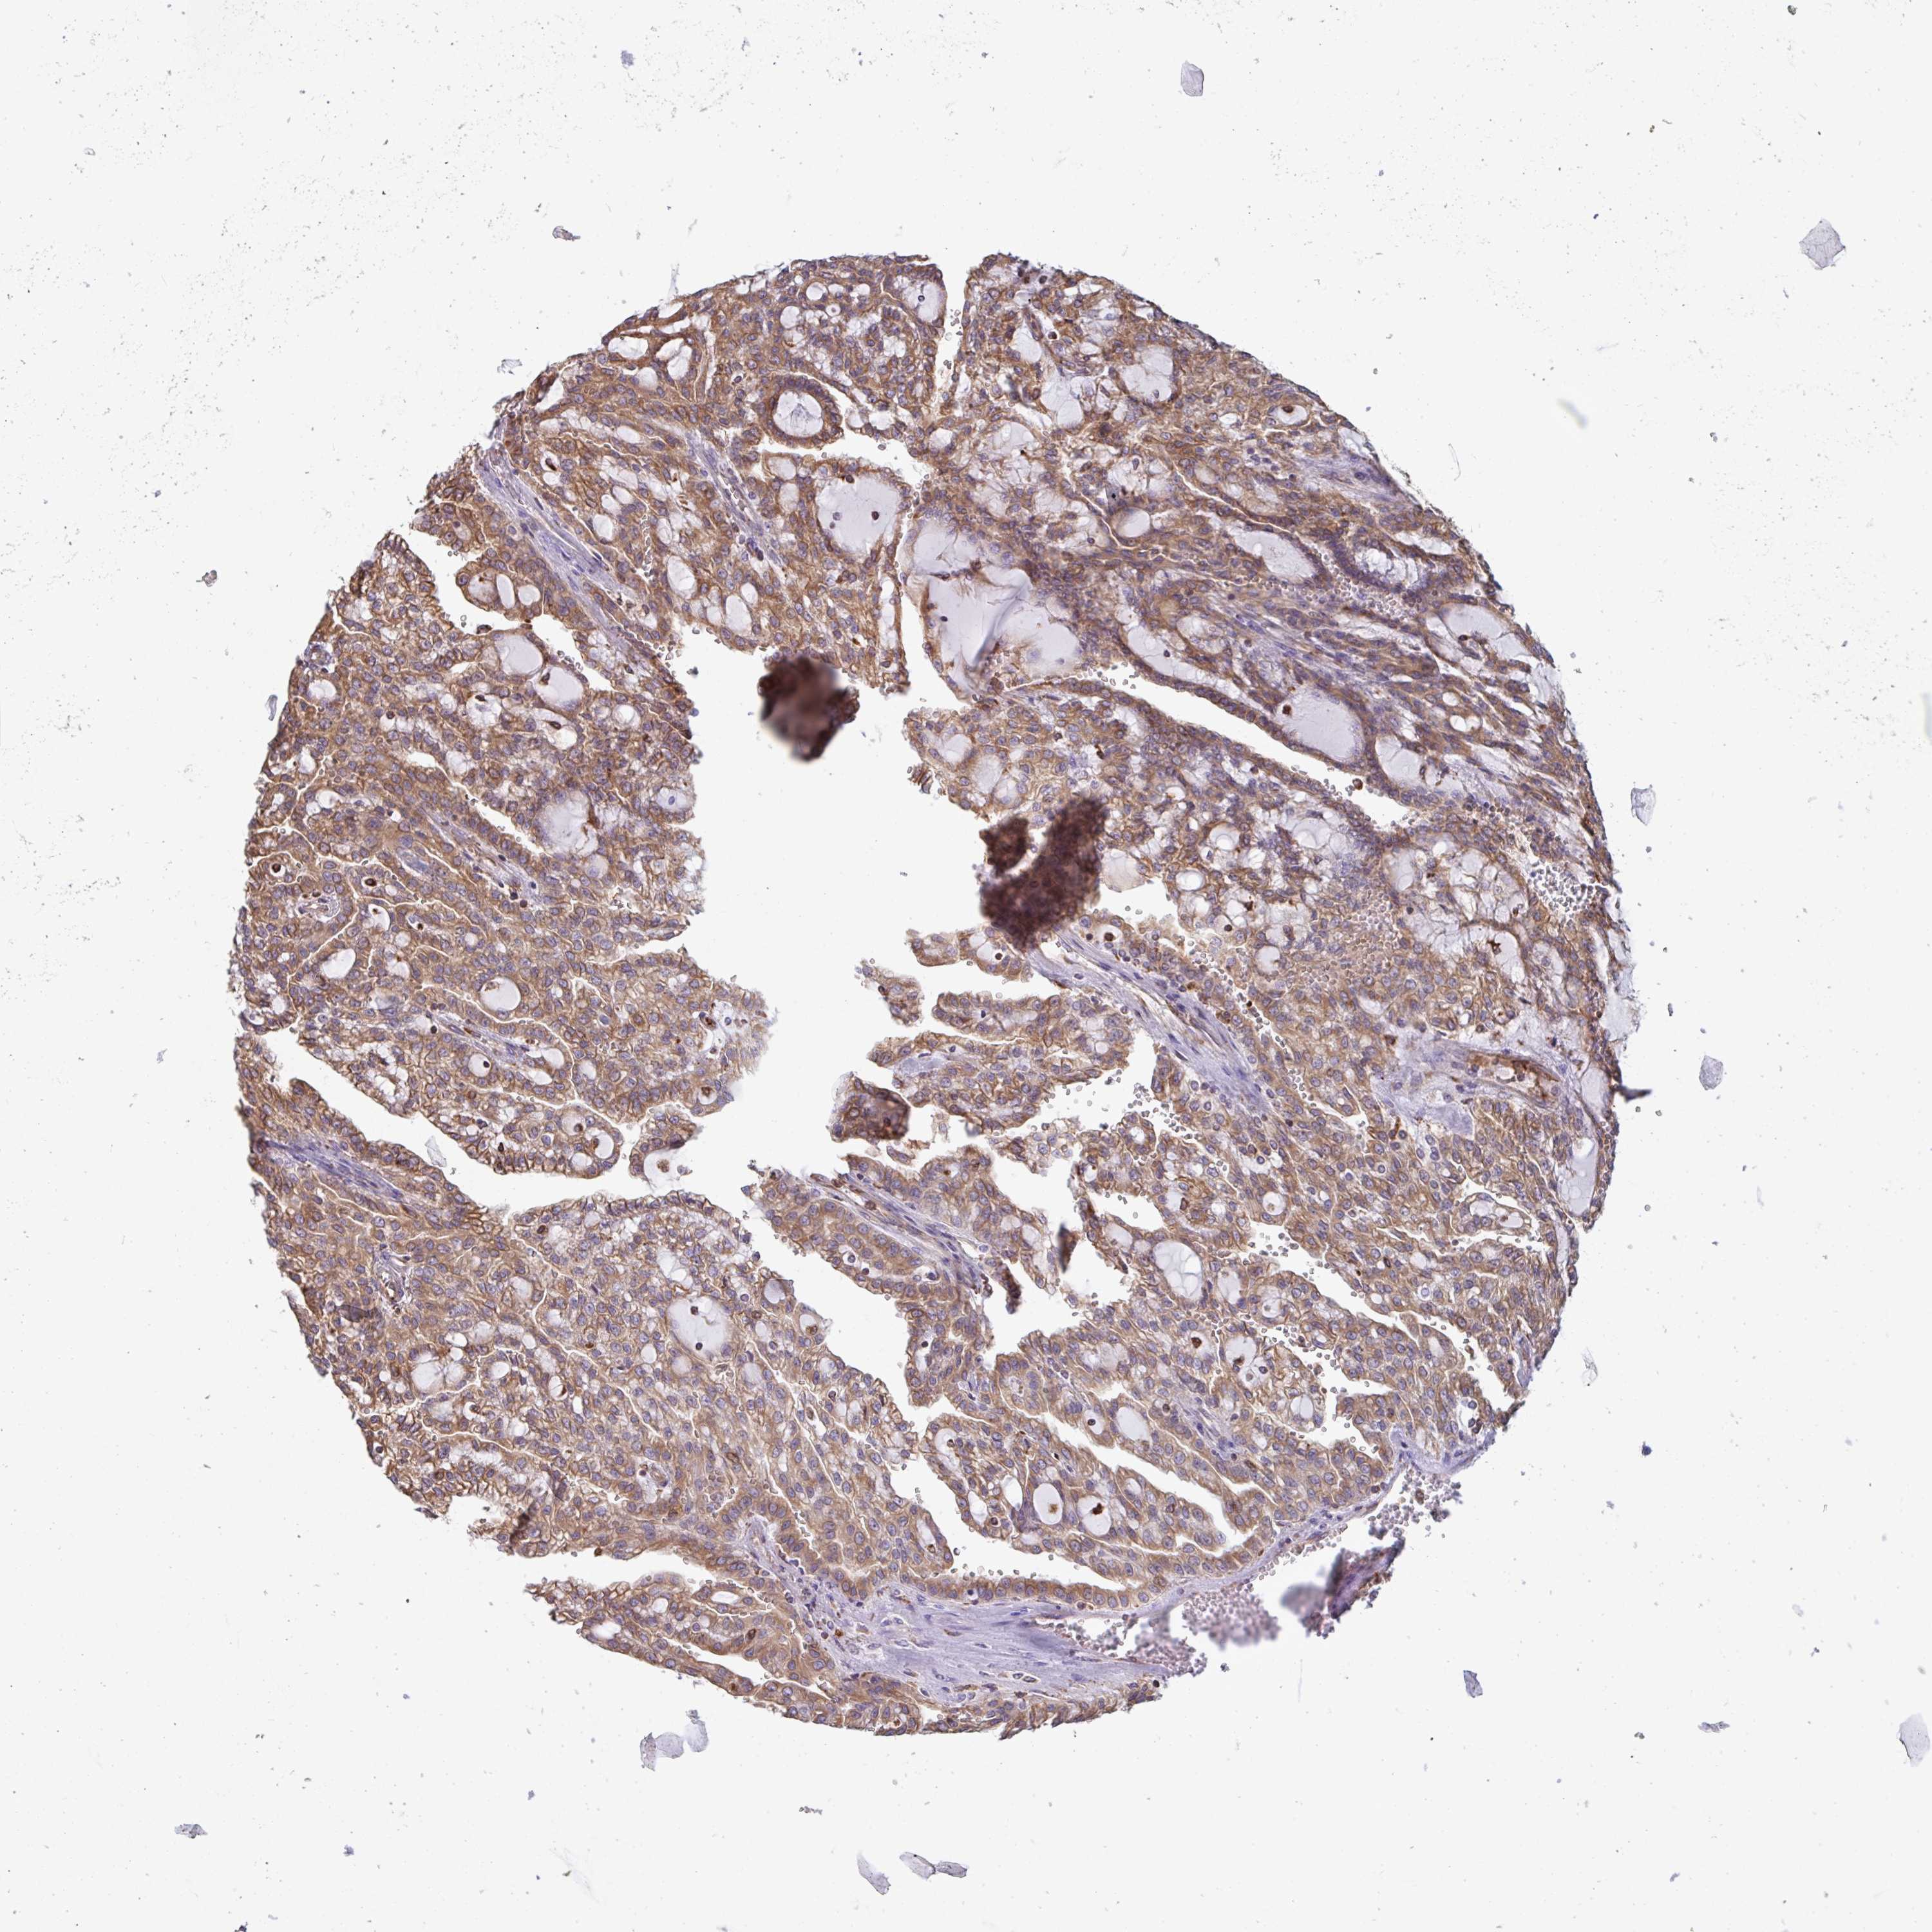

KIDNEY RENAL CLEAR CELL CARCINOMA (VALIDATION) - Interactive survival scatter ploti

The Survival Scatter plot shows the clinical status (i.e. dead or alive) for all individuals in the patient cohort, based on the same data that underlies the corresponding Kaplan-Meier plots. Patients that are alive at last time for follow-up are shown in blue and patients who have died during the study are shown in red.

The x-axis shows the expression levels (FPKM) of the investigated gene in the tumor tissue at the time of diagnosis. The y-axis shows the follow-up time after diagnosis (years). Both axes are complimented with kernel density curves demonstrating the data density over the axes. The top density plot shows the expression levels (FPKM) distribution among dead (red) and alive patients (blue). The right density plot shows the data density of the survived years of dead patients with high and low expression levels respectively, stratified using the cutoff indicated by the vertical dashed line through the Survival Scatter plot. This cutoff is automatically defined based on the FPKM cutoff that minimizes the p-score. The cutoff can be changed by dragging the vertical line or by entering a cutoff value in the square labeled "Current cut-off".

Under the Survival Scatter plot the p-score landscape (black curve; left axis) is shown together with dead median separation (red curve; right axis). Dead median separation is the difference in median mRNA expression between patients who have died with high and low expression, respectively. It is calculated as follows: median FPKM expression of dead patients with high expression - median FPKM expression of dead patients with low expression. This is intended to aid the user in visually exploring custom cutoffs and the associated p-scores and dead median separation.

Individual patient data is displayed and can be filtered by clicking on one or more of the category buttons on the top of the page. Categories describing expression level and patient information include: high, low, alive, dead, female, male and tumor stages. The scale of the x-axis can be toggled between linear and log-scale by clicking on the "x log" button. Mouse-over function shows TCGA ID, patient information and mRNA expression (FPKM) for each patient.

& Survival analysisi

Kaplan-Meier plots summarize results from analysis of correlation between mRNA expression level and patient survival. Patients were divided based on level of expression into one of the two groups "low" (under cut off) or "high" (over cut off). X-axis shows time for survival (years) and y-axis shows the probability of survival, where 1.0 corresponds to 100 percent.

DOK4 is not prognostic in Kidney Renal Clear Cell Carcinoma (validation)

Best expression cut offi

Based on the FPKM value of each gene, patients were classified into two groups and association between prognosis (survival) and gene expression (FPKM) was examined. The best expression cut-off refers the FPKM value that yields maximal difference with regard to survival between the two groups at the lowest log-rank P-value. Best expression cut-off was selected based on survival analysis .

When clicking on this number, the vertical dashed line indicating cut-off, the interactive survival plot, and the Kaplan-Meier curve will be adjusted to show results based on the best expression cut-off.

: 41.57

P scorei

Log-rank P value for Kaplan-Meier plot showing results from analysis of correlation between mRNA expression level and patient survival.

N/A

Average pTPM 60.7

Number of samples 100